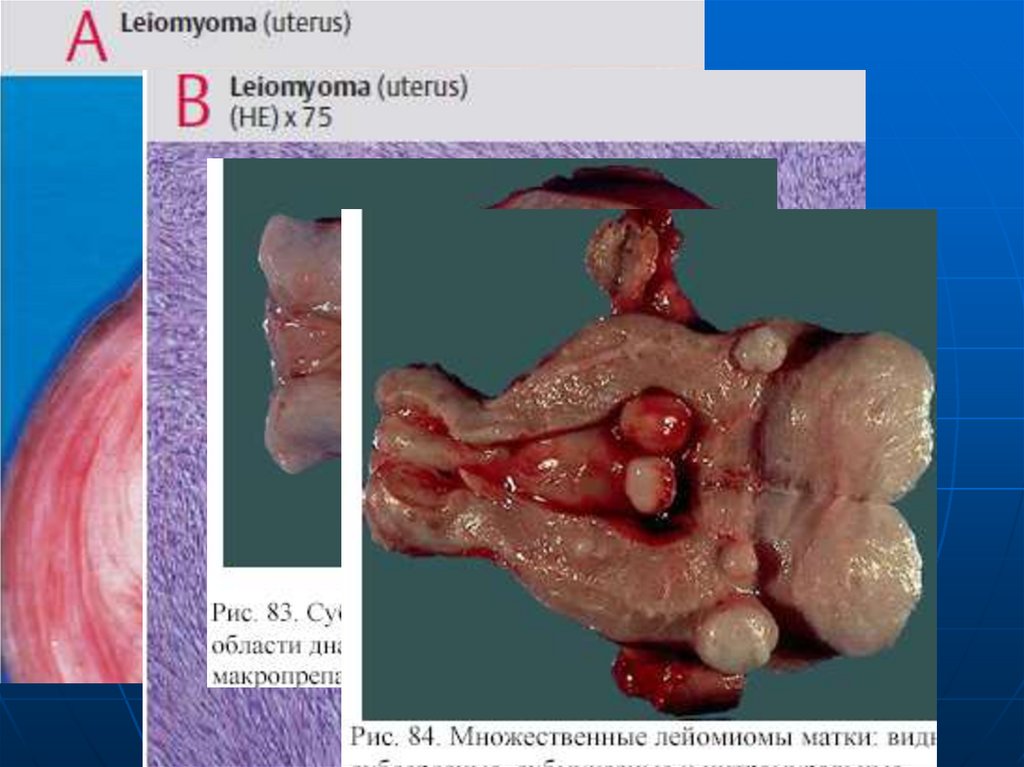

Миома - доброкачественная опухоль из

гладкомышечных волокон тела

матки. По локализации:

• Субмукозные;

• Интрамуральные;

• Субсерозные.

По количеству: одиночные и множественные.

По размерам: от 1 см до 20 см. Если миома

состоит из гладкомышечной ткани, то

называется лейомиомой. Фибромиома – с

добавлением соединительной ткани

(плотная). Миома может малигнизироваться в

лейомиосаркому.

Лейомиома матки